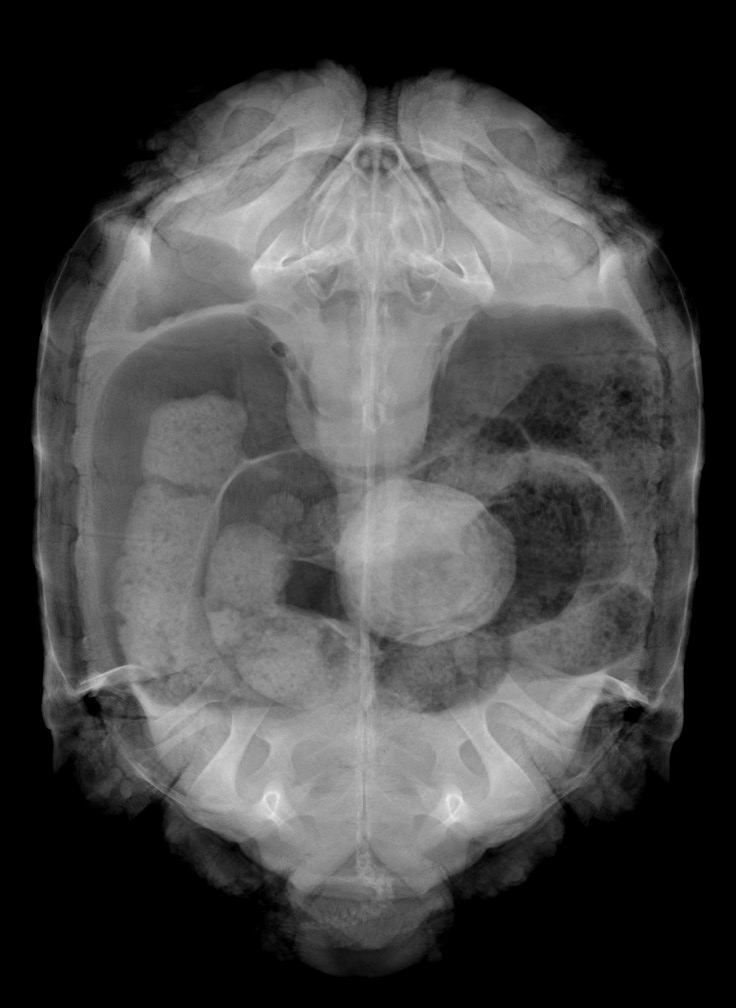

膀胱結石が見られるケヅメリクガメのレントゲン写真。

リクガメは体内の老廃物を尿酸という固形物にして排泄します。

これが膀胱の中に蓄積して巨大な膀胱結石となってしまうことはよく見られます。

一度結石となった尿酸は溶けることはないので、自力での排泄が困難である場合、手術による摘出が必要となります。